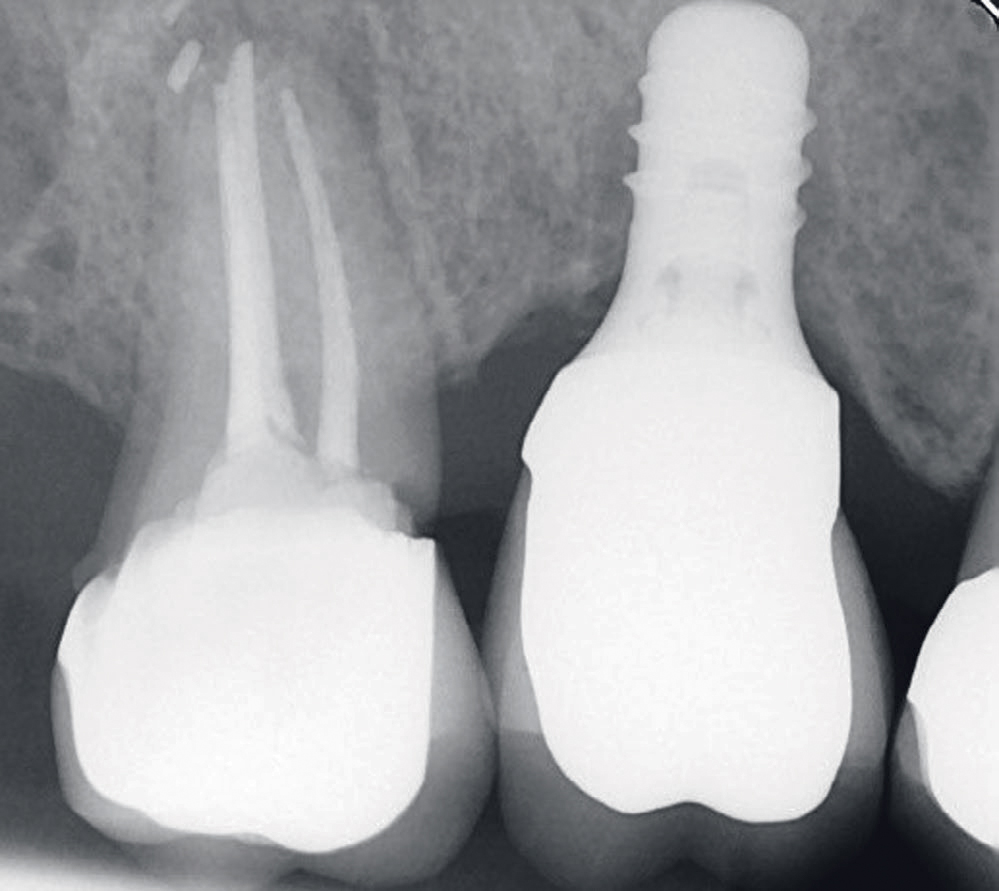

Status presens: ved ekstraoral undersøkelse av hode-/halsregion, kjeveledd og tyggemuskulatur ble det påviste stram tyggemuskulatur; ellers ingen anmerkning. Intraoral undersøkelse viste et velkonservert tannsett, god munnhygiene, men tydelig okklusal slitasje på tenner/kronerestaureringer. Pasienten informerte om tanngnissing. Mobilitet ble diagnostisert i bukko-palatinal retning på implantatkrone regio 16. Kronen hadde en voluminøs utforming og okklusalt var det tydelige slitasjeskader i porselenet særlig i det mesio-palatinale cuspområdet (figur 1). Det var ikke mulig å måle lommer eller blødning rundt implantatet. Røntgen 1. kvadrant viste tannretinerte kroner 17,15 og implantatstøttet krone regio 16. Endodontisk behandlet 17 viste apikal forandring, overskudd av rotfyllingsmateriale og sekundær karies i kronekanten mesialt, som henvisende tannlege har valgt å observere. Implantat regio 16 manglet benkontakt langs hele implantatets lengde (figur 2 og 3).

Figur 2. Røntgenbilde fra april 2018 før fjerning av kronen viser endret benmorfologi langs hele implantatets lengde.

Figur 3. Røntgenbilde fra april 2018 etter fjerning av kronen dokumenterer også endret benmorfologi langs implantatet.